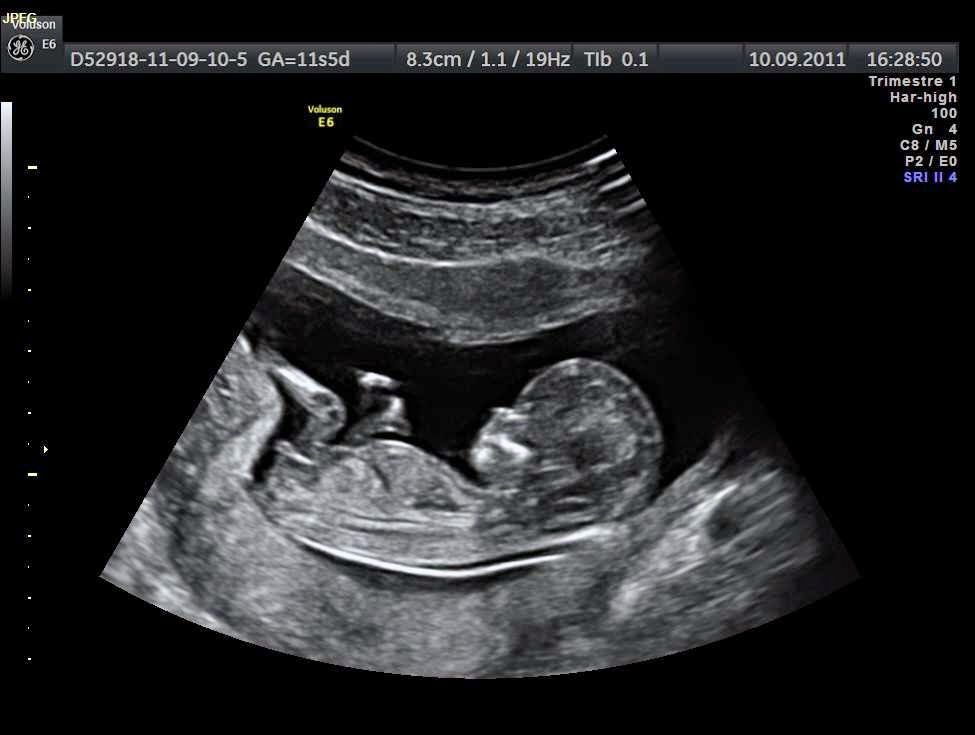

Kích thước của thai nhi 14 tuần tuổi

Bước vào tuần thai thứ 14, "thiên thần nhỏ" của bạn sẽ có kích thước xấp xỉ một quả chanh, bé nặng từ 43 – 50 gam, chiều dài từ đầu đến mông của thai nhi 14 tuần rơi vào khoảng 9 cm. Để bé có thể đạt được các chỉ số phát triển tiêu chuẩn như trên, mẹ bầu cần có chế độ sinh hoạt, ăn uống, vận động và nghỉ ngơi hợp lý.

Thai nhi 14 tuần có kích thước tương tự như 1 quả chanh

Các chỉ số về cân nặng và kích thước của thai nhi 14 tuần nếu quá cao hoặc quá thấp đều ảnh hưởng nghiêm trọng đến sức khỏe, trí tuệ và sự phát triển của trẻ sau này. Do đó, mẹ bầu cần đặc biệt lưu ý, thường xuyên đi siêu âm để có thể nắm bắt và kiểm soát được thể trạng của trẻ.

- Thai nhi tuần thứ 14, khi đi siêu âm, bạn đã có thể nghe được nhịp tim của bé một cách rõ ràng. Đây là thời điểm mà trái tim bé nhỏ ấy đang ”tăng tốc” để hoàn thiện. Trong một ngày, tim của bé có khả năng bơm được 25 lít máu /ngày và sẽ tăng dần lên theo số tăng của tuần thai.

Hình ảnh thai nhi 14 tuần